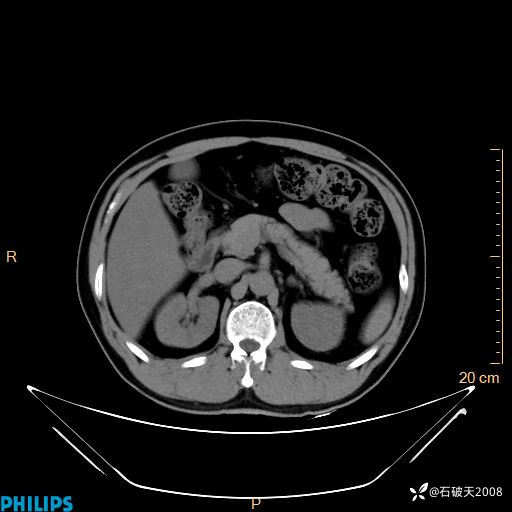

增强轴位